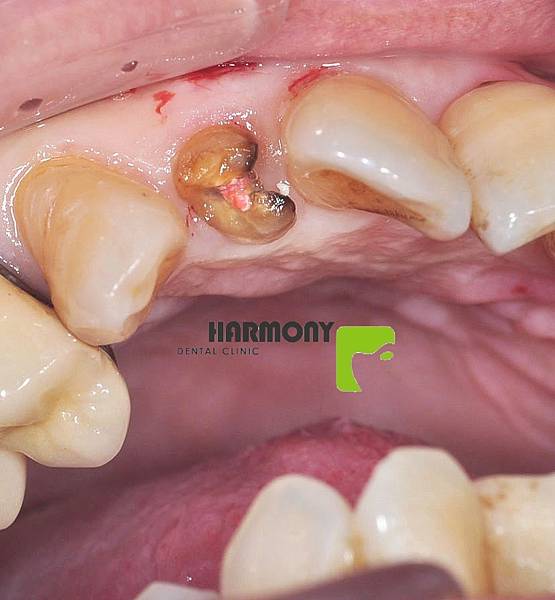

術前(部位:左上)

術前(部位:左上)骨頭明顯缺損

病患根管治療過後牙齒斷裂無法保留

經診斷後未有根尖發炎也未傷及骨頭

術前(部位:左上)

術前(部位:左上) 術前(部位:左上)

術前(部位:左上) 病患根管治療過後牙齒斷裂無法保留